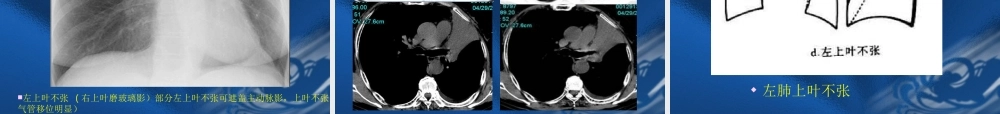

呼吸系统基本病变的影像学表现第一节支气管阻塞性改变第二节肺部改变第三节肺门的改变第四节胸膜病变第五节纵隔的改变第六节膈的改变第一节支气管阻塞性改变第一节支气管阻塞性改变原因:腔内性:肿瘤、异物、炎症、结核、先天性狭窄。腔外性:淋巴结增大压迫。后果:部分阻塞:阻塞型肺气肿。完全阻塞:阻塞型肺不张。第一节支气管阻塞性改变第一节支气管阻塞性改变一、阻塞型肺气肿(obstructiveemphysema)1、两肺阻塞性肺气肿:见于慢支及支气管哮喘。影像表现:肺野透过度增加,与呼吸时相关系不大;肺纹理稀疏变细,可见肺大泡。以双上肺为多见,横膈低平,活动度减低;胸廓呈桶状,肋间隙增宽;心影狭长呈垂位心型,心后间隙增宽。如果出现双下肺透过度增加可能要考虑a1-抗胰蛋白酶缺乏症.第一节支气管阻塞性改变第一节支气管阻塞性改变2、局限性阻塞性肺气肿一侧性肺气肿:一叶性肺气肿:影像表现:肺内表现同上;纵隔向健侧移位或移位不明显。气管内异物可表现为纵隔摆动。支气管断层或造影有利于诊断。正常肺组织病理图肺泡肺泡壁终末细支气管肺气肿:终末细支气管远侧气腔持久性异常增大,伴受累气腔壁的破坏小叶中央型:两肺弥漫分布,直径小于1cm,无明显的壁,其内见小点状中央细支气管动脉。全小叶型:两肺弥漫分布圆形类圆形的无壁低密度区间隔旁型:位于胸膜下(肋胸膜、膈胸膜及纵隔胸膜)呈带状分布的不规则空气密度次级肺小叶:肺小叶,最小的肺组织单位,小叶细支气管和小叶动脉,约1-2.5cm大小,分出3-5支终末细支气管终末细支气管以远的肺结构为腺泡,约4-7mm小叶中心型肺气肿全小叶型肺气肿小叶中央型全小叶型间隔旁型肺纹理减少、横膈变平、桶状胸、心影狭长。阻塞性细支气管炎(BronchiolitisObliterans)指细支气管发炎的病变,导致支气管壁纤维化以及管腔阻塞。阻塞性细支气管炎(BronchiolitisObliterans)呈现—马赛克灌注,磨玻璃密度区肺血管增粗。支扩肺血管增粗第一节支气管阻塞性改变第一节支气管阻塞性改变二、阻塞性肺不张(obstructiveatelectasis)1、一侧性肺不张:一侧主支气管完全性阻塞的后果。影像表现:患侧肺野均匀一致密度增高影;胸廓塌陷,肋间隙变窄;纵隔向患侧移位;患侧膈肌升高;健侧代偿性肺气肿。第一节支气管阻塞性改变第一节支气管阻塞性改变2、肺叶不张:肺叶支气管完全性阻塞的后果。肺叶不张的共同...